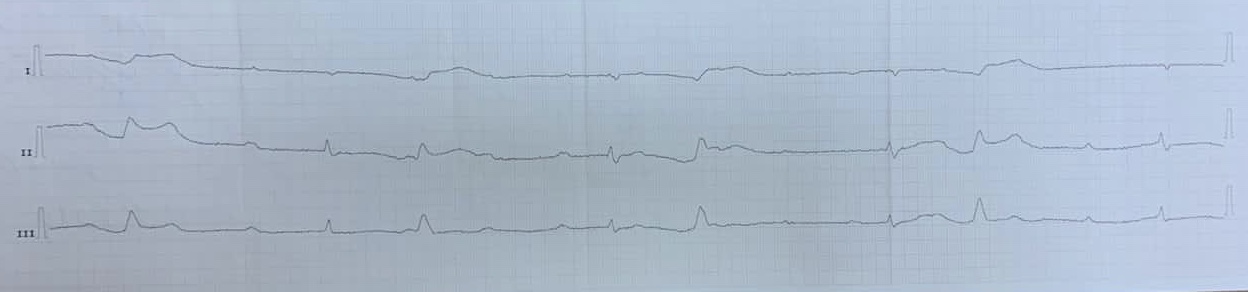

ЖТ

Вложения:

IMG_4388.JPG

IMG_4388.JPG [ 385.05 KiB | Просмотров: 32488 ]